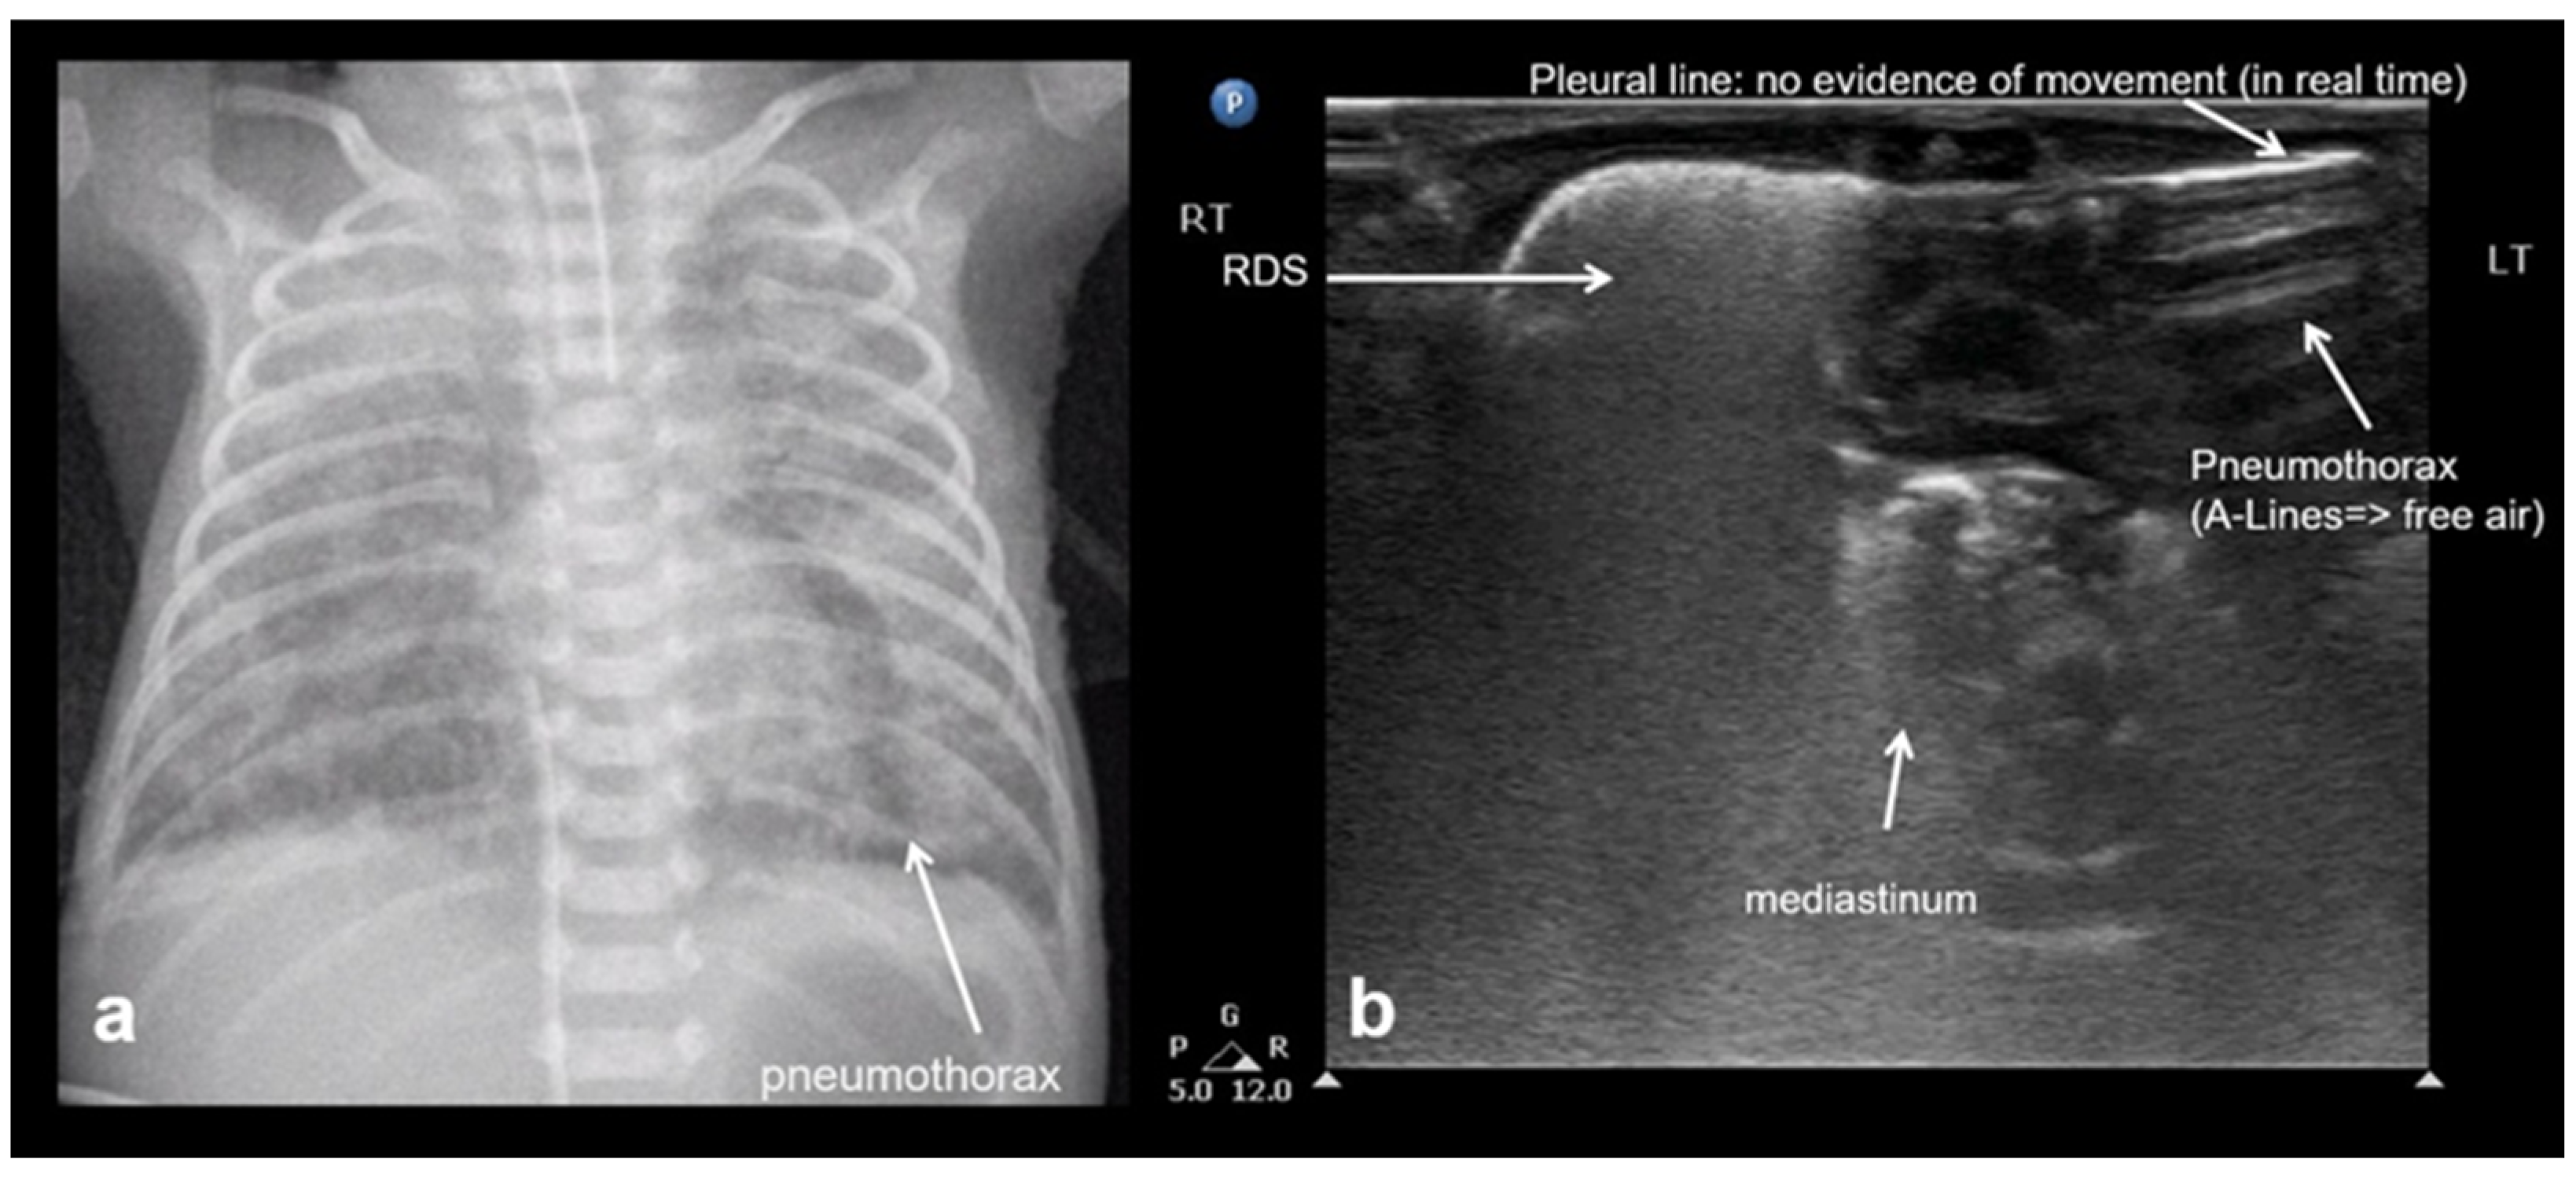

3.2.8. Pneumothorax